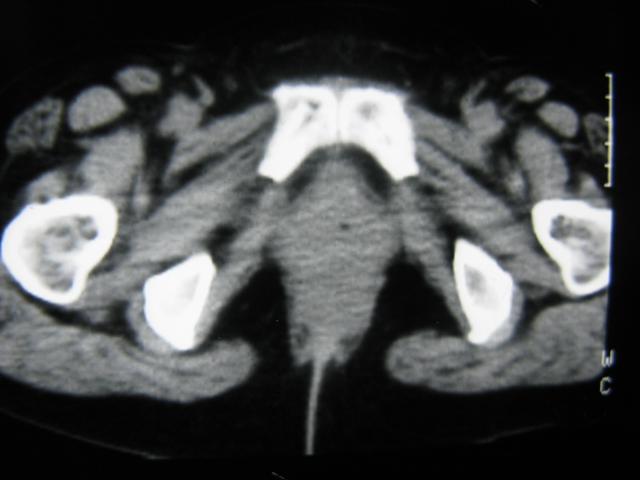

患者,女,64岁,2002年诊断为宫颈癌,当时只做过放,化疗。现在诊断:(1)宫颈癌。(2)直肠癌。请同道们讨论,探讨。另外肠壁为啥密度这么高,ct值约112hu。患者没有做过增强和造影。

高密度的不是肠管影,是肠管内的粪便影

患者直肠病变,排便不畅,粪便硬结造成,更高密度如钡灌肠者都可出现

难定宫径癌,直肠癌

我也碰到过几例,最离奇的一例是全结肠呈造影样高密度,患者直肠癌(首次发现),以往没有吃药,只有约半年时间长的胃纳差,排便不畅(据患者说每次大便只能拉出少许黄水)

不一定有意义,可清洁灌肠后复查